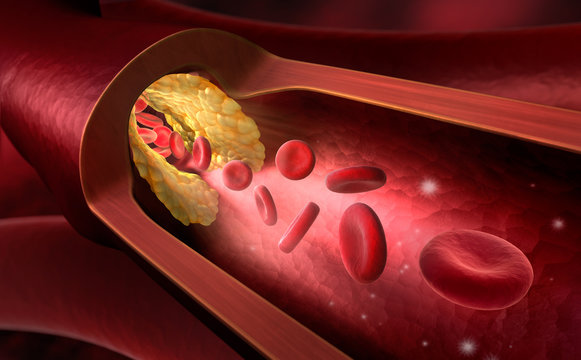

Холестерин в организме: влияние и функции (схемы и диаграммы)